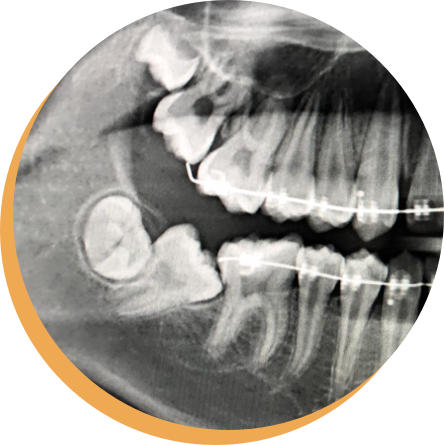

Wisdom teeth can cause dental problems if they become impacted (wisdom tooth pushing against another tooth or gum). Impaction can lead to tooth decay, periodontal (gum) disease or infection. Wisdom teeth may be associated with cysts and tumours of the jaws. Problematic wisdom teeth can lead to painful chewing and bad breath.